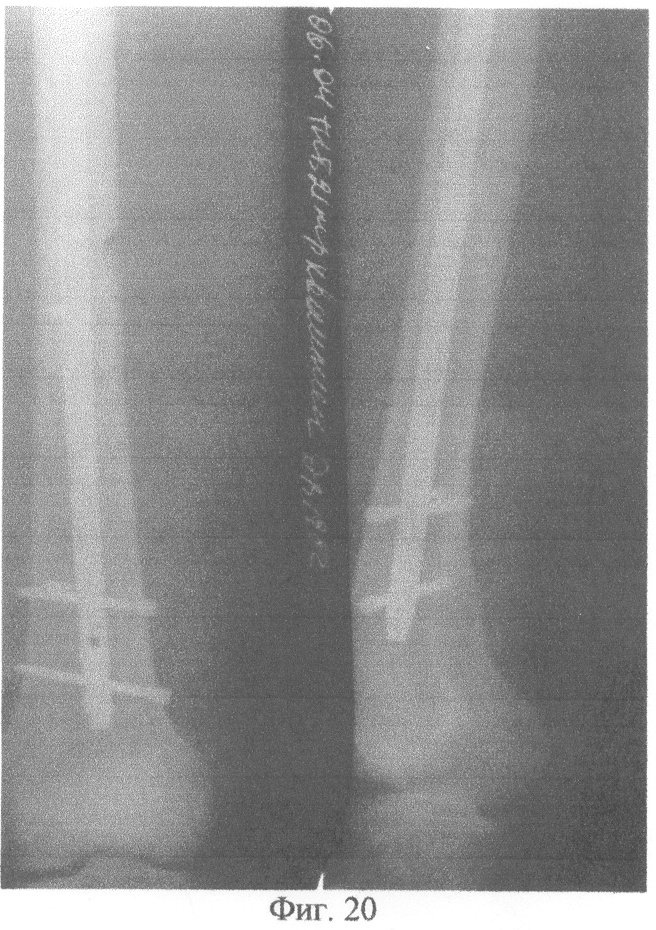

На фиг.1 изображено определение длины канюлированного стержня по отметке на шкале направляющей спицы. На фиг.2 – приведение в соответствие отверстий в блоке дистального целенаправителя отверстиям на рабочем конце канюлированного стержня с помощью контрольного инструмента. На фиг.3 – введение подготовленного канюлированного стержня по направляющей спице в костно-мозговой канал. На фиг.4 – выдвижение держателем направляющей спицы. На фиг.5 – контроль прохождения сверла через ниже расположенное отверстие на рабочем конце канюлированного стержня с помощью направляющей спицы и по отметке на шкале направляющей спицы. На фиг.6 – контроль прохождения блокирующего винта через ниже расположенное отверстие на рабочем конце канюлированного стержня с помощью направляющей спицы и по отметке на шкале направляющей спицы. На фиг.7 – контроль прохождения сверла через выше расположенное отверстие на рабочем конце канюлированного стержня и по отметке на шкале направляющей спицы. На фиг.8 – контроль прохождения блокирующего винта через выше расположенное отверстие на рабочем конце канюлированного стержня с помощью направляющей спицы и по отметке на шкале направляющей спицы. На фиг.9 – прохождение сверла впереди канюлированного стержня и проведение контроля отсутствия сверла в ниже расположенном отверстии на рабочем конце канюлированного стержня с помощью направляющей спицы и по отметке на шкале направляющей спицы. На фиг.10 – прохождение сверла позади канюлированного стержня и проведение контроля отсутствия сверла в ниже расположенном отверстии на рабочем конце канюлированного стержня с помощью направляющей спицы и по отметке на шкале направляющей спицы. На фиг.11 – сопротивление сверлу канюлированным стержнем и проведение контроля отсутствия сверла в ниже расположенном отверстии на рабочем конце канюлированного стержня с помощью направляющей спицы и по отметке на шкале направляющей спицы. На фиг.12 – определение спицей Киршнера ниже расположенного отверстия на рабочем конце канюлированного стержня и проведение контроля положения спицы Киршнера в ниже расположенном отверстии на рабочем конце канюлированного стержня с помощью направляющей спицы и по отметке на шкале направляющей спицы. На фиг.13 – контроль прохождения сверла через ниже расположенное отверстие на рабочем конце канюлированного стержня с помощью направляющей спицы и по отметке на шкале направляющей спицы. На фиг.14 – контроль прохождения блокирующего винта через ниже расположенное отверстие на рабочем конце канюлированного стержня с помощью направляющей спицы и по отметке на шкале направляющей спицы. На фиг.15 – сопротивление сверлу канюлированным стержнем и проведение контроля отсутствия сверла в выше расположенном отверстии на рабочем конце канюлированного стержня с помощью направляющей спицы и по отметке на шкале направляющей спицы. На фиг.16 – определение спицей Киршнера выше расположенного отверстия на рабочем конце канюлированного стержня и проведение контроля положения спицы Киршнера в выше расположенном отверстии на рабочем конце канюлированного стержня с помощью направляющей спицы и по отметке на шкале направляющей спицы. На фиг.17 – контроль прохождения сверла через выше расположенное отверстие на рабочем конце канюлированного стержня с помощью направляющей спицы и по отметке на шкале направляющей спицы. На фиг.18 – контроль прохождения блокирующего винта через выше расположенное отверстие на рабочем конце канюлированного стержня с помощью направляющей спицы и по отметке на шкале направляющей спицы. На фиг.19 – рентгенограмма левой бедренной кости в двух проекциях больного Квашнина Д.В. до операции. На фиг.20 – рентгенограмма левой бедренной кости в двух проекциях больного Квашнина Д.В. после операции. На фиг.21 – рентгенограмма костей левой голени в двух проекциях больной Корхалевой Е.Н. до операции. На фиг.22 – рентгенограмма костей левой голени в двух проекциях больной Корхалевой Е.Н. после операции.

Пример 1. Больной Квашнин Д.В., 20 лет, медицинская карта №12956, госпитализированный в ортопедотравматологическое отделение Городской клинической больницы №21 города Уфы через 2 часа после травмы с диагнозом: закрытый оскольчатый перелом средней трети левой бедренной кости со смещением отломков.

Рентгенограмму левой бедренной кости при поступлении см. на фиг.19. После обследования и предоперационной подготовки произведена операция: блокирующий интрамедуллярный остеосинтез отломков левой бедренной кости.

Под интубационным наркозом на ортопедическом столе произведена закрытая репозиция отломков левой бедренной кости, в костно-мозговой канал введена направляющая спица. Произведена контрольная рентгенограмма левой бедренной кости в двух проекциях передвижным рентгенаппаратом. По отметке на шкале направляющей спицы определена длина канюлированного стержня (460 мм). Произведена подготовка дистального целенаправителя: приведены в соответствие отверстия в блоке дистального целенаправителя отверстиям на рабочем конце канюлированного стержня с помощью контрольного инструмента. Введен в костно-мозговой канал по направляющей спице подготовленный канюлированный стержень длиной 460 мм. Держателем выдвинута направляющая спица. Через нижнее отверстие в блоке дистального целенаправителя сверлом сформирован канал в близлежащем кортикальном слое кости. Продолжая сверление, сверло не проходило в ниже расположенное отверстие на рабочем конце канюлированного стержня вследствие деформации рабочего конца канюлированного стержня во время введения его в костно-мозговой канал. Отсутствие сверла в ниже расположенном отверстии рабочего конца канюлированного стержня контролировали следующим образом: держателем направляющая спица проведена по каналу стержня в дистальном направлении, она не встретила сопротивления сверла на уровне ниже расположенного отверстия на рабочем конце канюлированного стрежня, прошла дистальнее; по отметке на шкале направляющей спицы показатель равен 460 мм, то есть больше разницы между длиной канюлированного стержня (460 мм) и расстоянием от рабочего конца канюлированного стержня до уровня ниже расположенного отверстия на рабочем конце канюлированного стержня (20 мм). Удалено сверло, снят дистальный целенаправитель. В отверстие в близлежащем кортикальном слое кости введена спица Киршнера, которой определено ниже расположенное отверстие на рабочем конце канюлированного стержня. Контроль положения спицы Киршнера в ниже расположенном отверстии на рабочем конце канюлированного стержня осуществлен следующим образом: держателем направляющая спица проведена в дистальном направлении по каналу стержня, она встретила сопротивление спицы Киршнера на уровне ниже расположенного отверстия на рабочем конце канюлированного стержня; по отметке на шкале направляющей спицы показатель равен 440 мм, что соответствует разнице между длиной канюлированного стержня (460 мм) и расстоянием от рабочего конца канюлированного стержня до уровня ниже расположенного отверстия на рабочем конце канюлированного стержня (20 мм). Сверлом соответственно направлению спицы Киршнера сформирован канал в кости, проходящий через ниже расположенное отверстие на рабочем конце канюлированного стержня. Контроль прохождения сверла через ниже расположенное отверстие на рабочем конце канюлированного стержня осуществлен следующим образом: держателем направляющая спица проведена в дистальном направлении по каналу стержня, она встретила сопротивление сверла на уровне ниже расположенного отверстия на рабочем конце канюлированного стержня; по отметке на шкале направляющей спицы показатель равен 440 мм, что соответствует разнице между длиной канюлированного стержня (460 мм) и расстоянием от рабочего конца канюлированного стержня до уровня ниже расположенного отверстия на рабочем конце канюлированного стержня (20 мм). Просверлен второй кортикальный слой кости, удалено сверло. В сформированный канал введен блокирующий винт. Контроль прохождения блокирующего винта через ниже расположенное отверстие на рабочем конце канюлированного стержня осуществлен следующим образом: держателем направляющая спица проведена в дистальном направлении по каналу стержня, она встретила сопротивление блокирующего винта на уровне ниже расположенного отверстия на рабочем конце канюлированного стержня; по отметке на шкале направляющей спицы показатель равен 440 мм, что соответствует разнице между длиной канюлированного стержня (460 мм) и расстоянием от рабочего конца канюлированного стержня до уровня ниже расположенного отверстия на рабочем конце канюлированного стержня (20 мм). Установлен дистальный целенаправитель. Через верхнее отверстие в блоке дистального целенаправителя сверлом сформирован канал в близлежащем кортикальном слое кости, продолжая сверление, сверло прошло в выше расположенное отверстие на рабочем конце канюлированного стержня. Контроль прохождения сверла через выше расположенное отверстие на рабочем конце канюлированного стержня осуществлен следующим образом: держателем направляющая спица проведена в дистальном направлении по каналу стержня, она встретила сопротивление сверла на уровне выше расположенного отверстия на рабочем конце канюлированного стержня; по отметке на шкале направляющей спицы показатель равен 415 мм, что соответствует разнице между длиной канюлированного стержня (460 мм) и расстоянием от рабочего конца канюлированного стержня до уровня выше расположенного отверстия на рабочем конце канюлированного стержня (45 мм). Просверлен второй кортикальный слой кости, удалено сверло. Через верхнее отверстие в блоке дистального целенаправителя введен в сформированный канал блокирующий винт. Контроль прохождения блокирующего винта через выше расположенное отверстие на рабочем конце канюлированного стержня осуществлен следующим образом: держателем направляющая спица проведена в дистальном направлении по каналу стержня, она встретила сопротивление блокирующего винта на уровне выше расположенного отверстия на рабочем конце канюлированного стержня; по отметке на шкале направляющей спицы показатель равен 415 мм, что соответствует разнице между длиной канюлированного стержня (460 мм) и расстоянием от рабочего конца канюлированного стержня до уровня выше расположенного отверстия на рабочем конце канюлированного стержня (45 мм). Произведено проксимальное блокирование канюлированного стержня. Сделана рентгенограмма в двух проекциях передвижным рентгенаппаратом (фиг.20). Продолжительность операции 1 час.